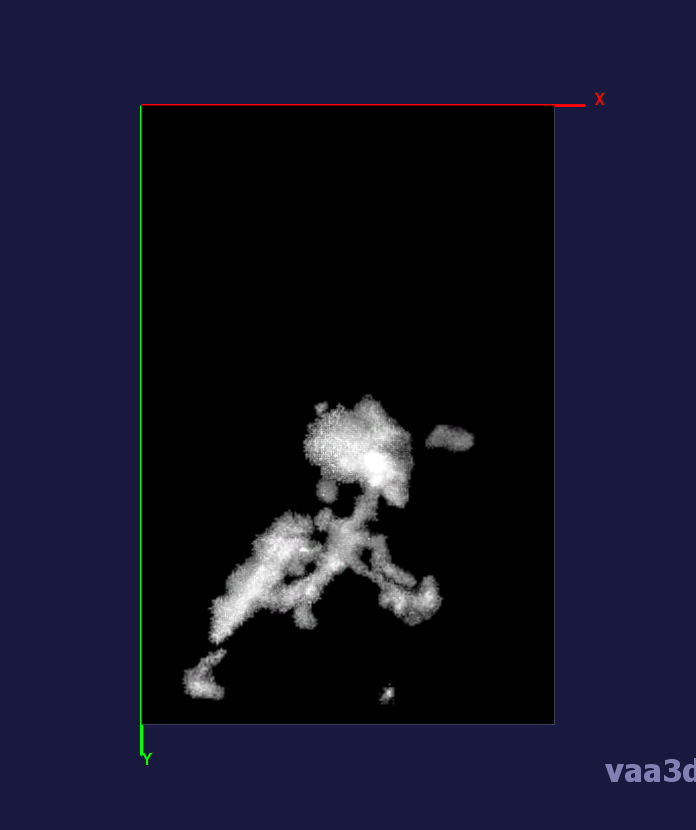

In our experiments, we compare the coupled TuFF-BFF microglia segmentation results with those given by L2S [21] and the Chan-Vese segmentation method [22]. The groundtruth in 3D was attained by manually tracing the object slice by slice from the z-stack. It must be noted that this was done by eye and could have some error. Figure 2 shows the visual comparison of the segmentation results for our dataset. Our result shown on the third column captures both the soma and processes. Figure 3 shows the Dice coefficient comparison of each segmentation method to the ground truth. Since the soma is much larger than the fine processes in the microglia, the processes have less volumetric impact on the similarity score. As explained in Section 1, segmenting the processes is important for quantifying the extension from the soma and its volume of surveillance. We use the Dice coefficient to quantitatively compare the ramification by taking the convex hull of the resulting segmentation. The Dice coefficient is a similarity measure that is computed using with where is the ground truth and is the compared image.

From Figure 4, the average Dice score for coupled TuFF-BFF was 0.77, compared to 0.53 for L2S [21] and .58 for Chan-Vese [22]. It must be noted that L2S required manual user initialization for each 2D image in the stack. While the Chan-Vese method has automatic seed selection, our coupled TuFF/BFF method was the only method that was a true 3D segmentation algorithm. L2S could not consistently capture the entire processes due to the intensity inhomogeneity throughout the object and background noise. The Chan-Vese segmentation could capture the extensions of the processes but did not work well with noise and attained false positives in the reconstruction. Since our method uses the tubular and blob information of the object to separate foreground and background, the segmentation only evolved within the object boundaries.

From the segmentation of microglia from 3D multiphoton images, we attained quantification of the ramification of the microglia processes using the index provided by Madry et al. The ramification index in Table 1 quantifies the extension of the processes from the soma. The ramification index of 1 is the soma with no ramification and a larger index denotes greater ramification. We compare the ramification index attained from the segmentation result from each method with that attained from the ground truth. The mean absolute error for coupled TuFF-BFF was 1.49 compared with 3.92 and 3.78 for L2S [21] and Chan-Vese [22], respectively.